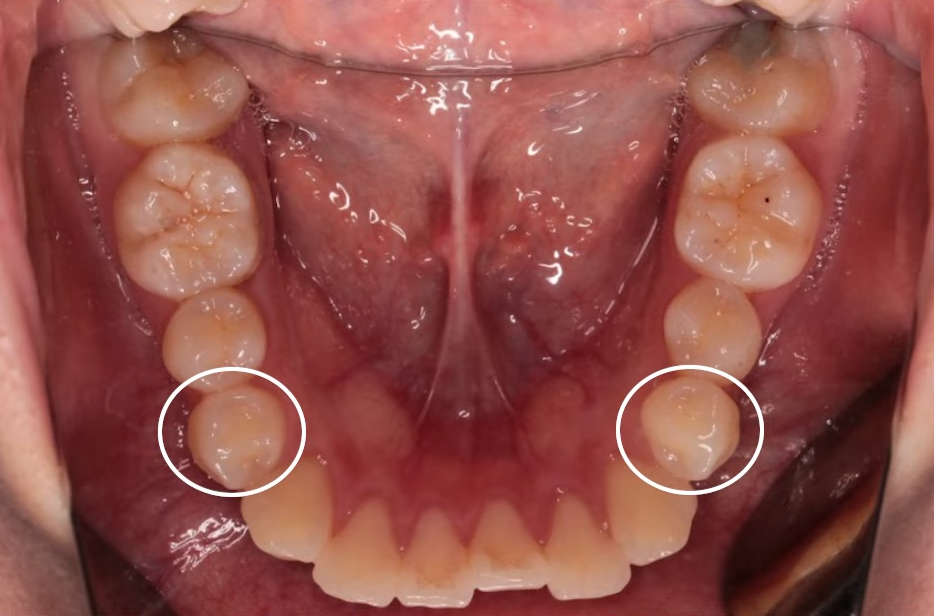

상악, 하악 각각 첫 번째 소구치를 발치했고,

인비절라인을 통해 치아를 뒤로 이동시키며 돌출을 점진적으로 개선했습니다.

뻐드러져 있던 치아 배열 모습이 정상적으로 돌아온 걸 확인하실 수 있을 겁니다.

총 치료 기간은 약 20개월이 걸렸는데요.

치료 전후 X-ray 사진을 비교해 보면,

기울어졌던 앞니가 정상 각도로 줄어들었고 자연스레 돌출입도 개선된 걸 볼 수 있지요.